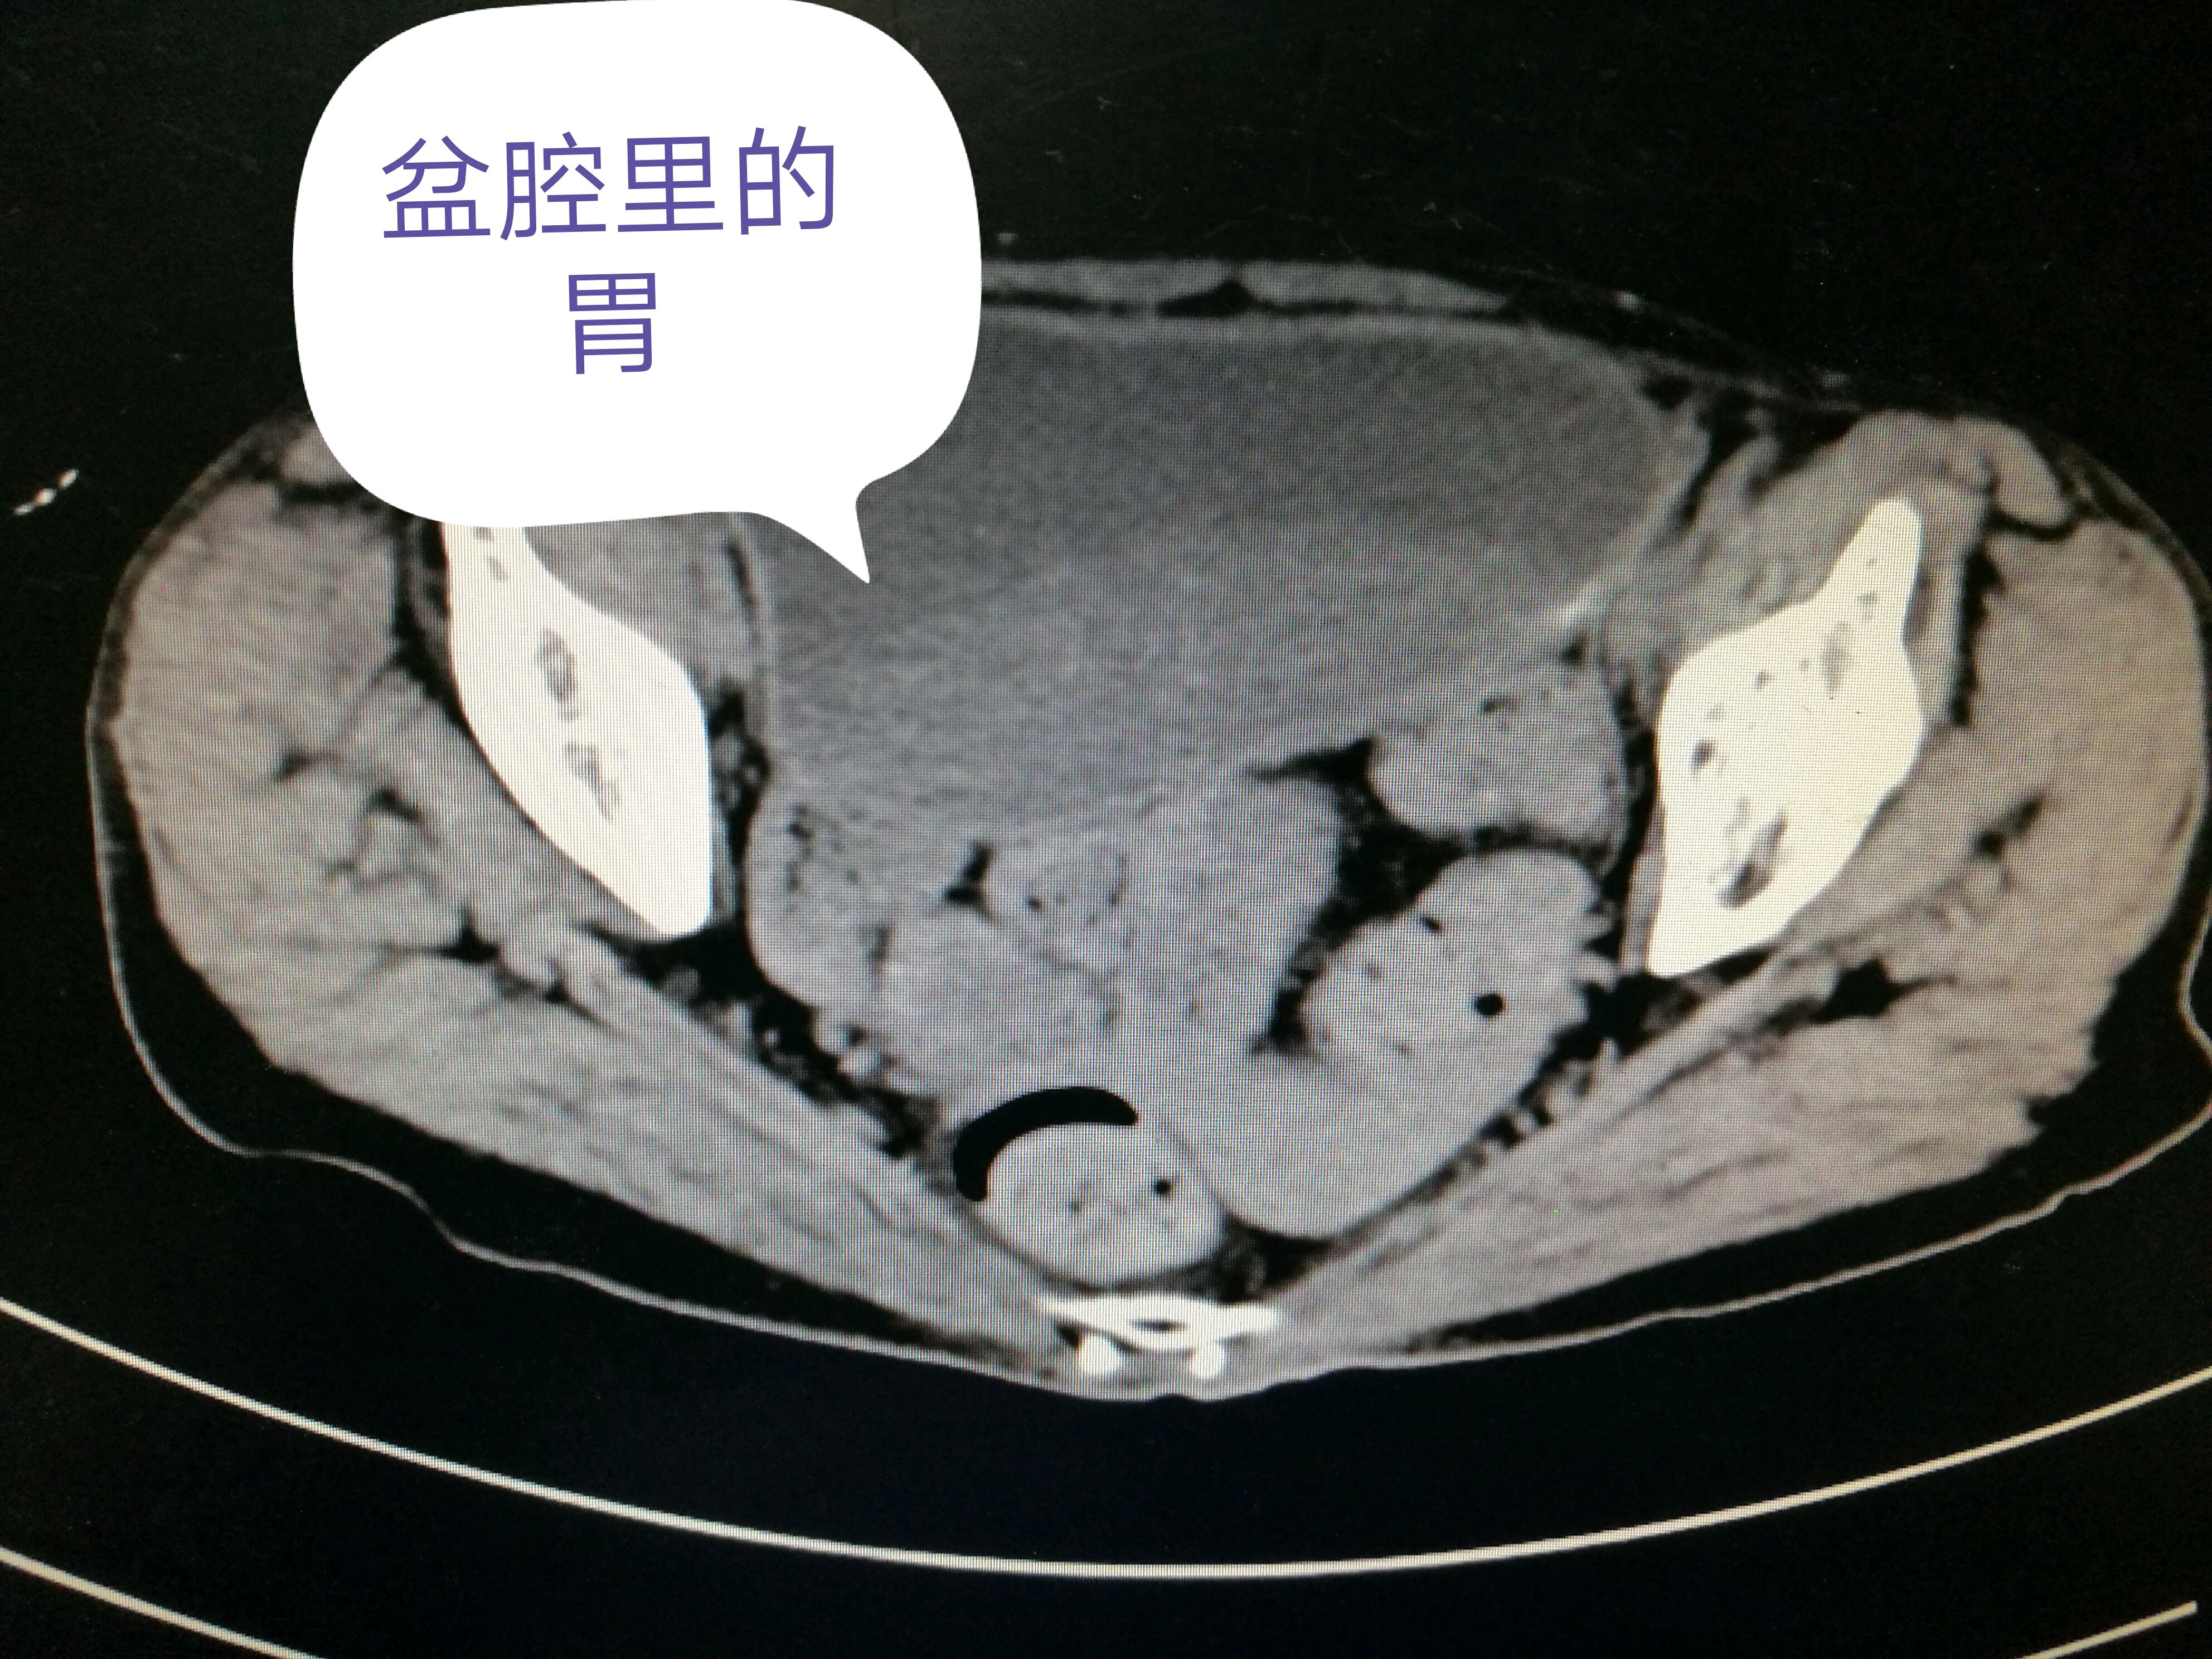

全腹ct平扫:胃潴留